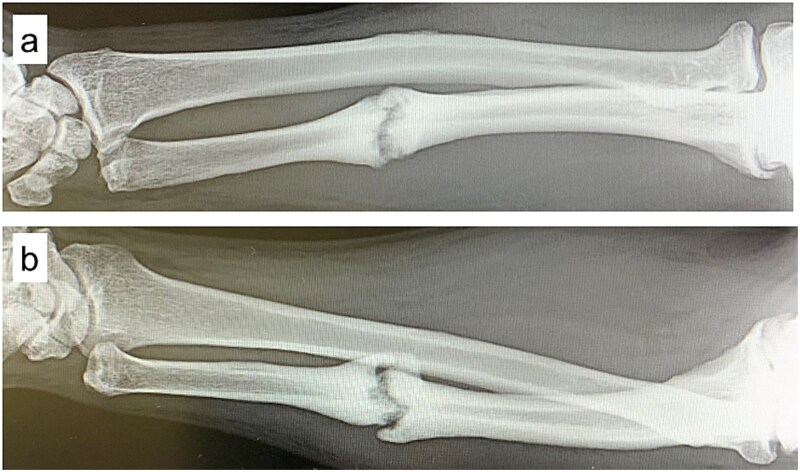

前驱疗法,包括注射高渗葡萄糖来刺激生长因子释放和促进组织愈合,最近作为一种难治性肌肉骨骼疾病的再生治疗得到了关注。我们报告一位54岁的男性,在空手道损伤后出现疼痛的尺干不愈合。保守治疗12个月后失败,患者出现持续性疼痛(数值评定量表[NRS]评分6)。超声引导下使用30%葡萄糖溶液进行前驱治疗,每2-3周进行5次。4周时发现骨痂形成,疼痛完全缓解(NRS评分0),患者在12周时恢复空手道训练。影像学证实15周愈合,无需固定或手术。这个病例强调了前驱疗法作为一种微创和有效的手术治疗疼痛性骨不连的替代方法的潜力。

Prolotherapy, involving hypertonic dextrose injections to stimulate growth factor release and promote tissue healing, has recently gained attention as a regenerative treatment for refractory musculoskeletal conditions. We report a 54-year-old man with a painful ulnar shaft nonunion after a karate injury. Conservative treatment failed over 12 months, and he presented with persistent pain (numeric rating scale [NRS] score 6). Ultrasound-guided prolotherapy using a 30% dextrose solution was performed in five sessions at 2-3 week intervals. Callus formation was noted at 4 weeks, pain completely resolved (NRS score 0), and the patient resumed karate at 12 weeks. Radiographic union was confirmed at 15 weeks without immobilization or surgery. This case highlights prolotherapy's potential as a minimally invasive and effective alternative to surgery for painful nonunion.